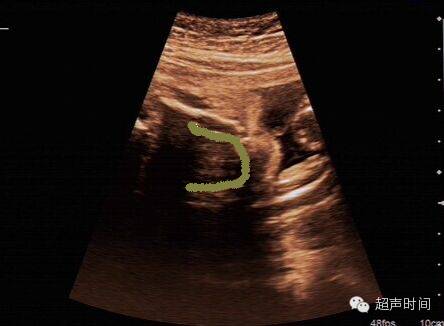

(盆底正中矢状切面valsalva状态)(盆底正中矢状切面静息状态)关爱女性